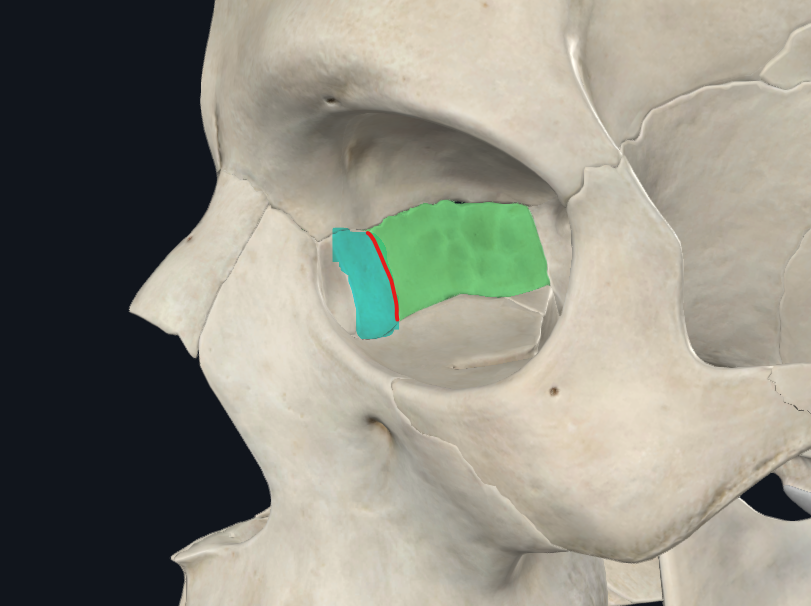

Lámina papirácea en cara lateral

Lámina papirácea del etmoides

Cara orbitaria del etmoides

Lámina delgada y lisa, frágil como un PAPIRO!

Forma una gran parte de la pared medial de la órbita